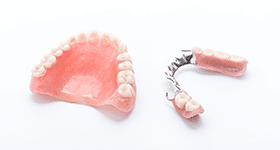

「歯を失ってしまったから……」と、好きなものを食べるのを諦めていませんか?

ブリッジは隣の歯への負担が大きすぎるし、入れ歯は噛む力が弱い、患者様のそんな不満を解消するために世界中で研究され、編み出されたのがインプラント治療です。固定式にして違和感や煩わしさを解消し、噛む力の負担の中心を歯茎の中の骨に求めることで、大きな力が加わっても大丈夫なように改良が重ねられました。新しい治療のため、費用が高額になるなど、欠点がないわけではありませんが、非常に画期的な治療方法と言えるでしょう。